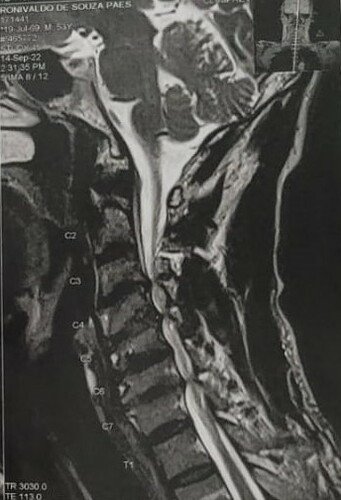

Hoje em decorrência de todos esses anos pegando no pesado, desenvolvi uma condição severa na coluna cervical chamada Mielopatia Espondilótica, que se trata de uma compressão da medula espinhal devido ao estreitamento degenerativo do canal vertebral. A coluna fica tão estreita que afeta a medula que é por onde passa os sinais do cabeça para o corpo. Esta doença me impede de trabalhar e até fazer coisas simples como ficar sentado em frente a TV.

A única forma de reverter o meu quadro é através de uma descompressão cirúrgica. Ou seja caso eu não realize a cirurgia, minha condição pode evoluir para cadeira de rodas.